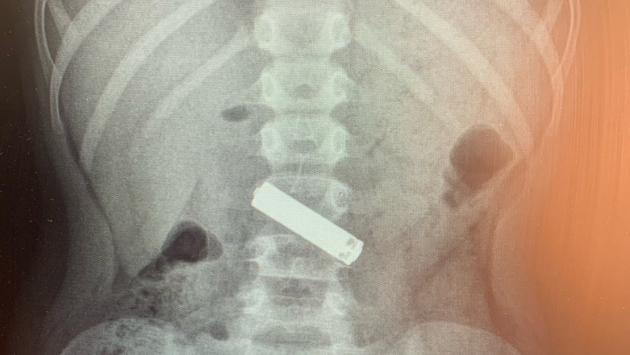

В Воронеже девятилетний ребенок случайно проглотил "мизинчиковую" батарейку во время игры.

На скорой ребенка экстренно доставили в БУЗ ВО "ОДКБ №2". В приемном отделении его осмотрели и сделали снимок органов брюшной полости.

В кратчайшие сроки было проведено эндоскопическое удаление инородного тела желудка – батарейка тип ААА, сообщает пресс-служба БУЗ ВО "ОДКБ №2".